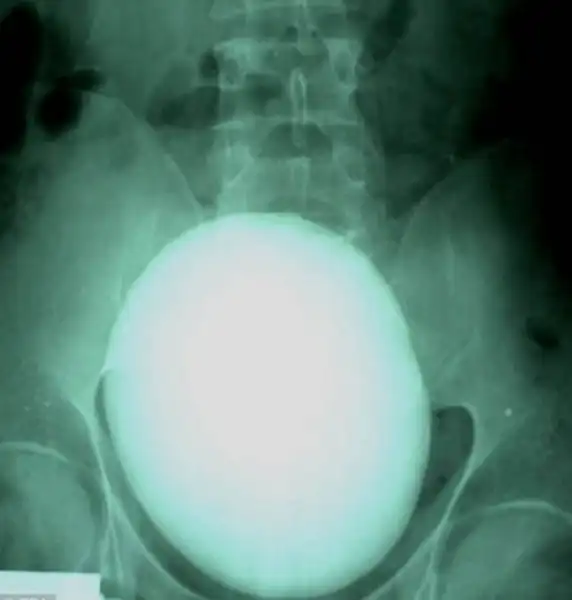

Вот такой вот 15-сантиметровый камень в почках весом 1,1 килограмм удалили пациенту из Венгрии.

Бутылка из-под «Пепси» в анусе 60-летнего мужчины.